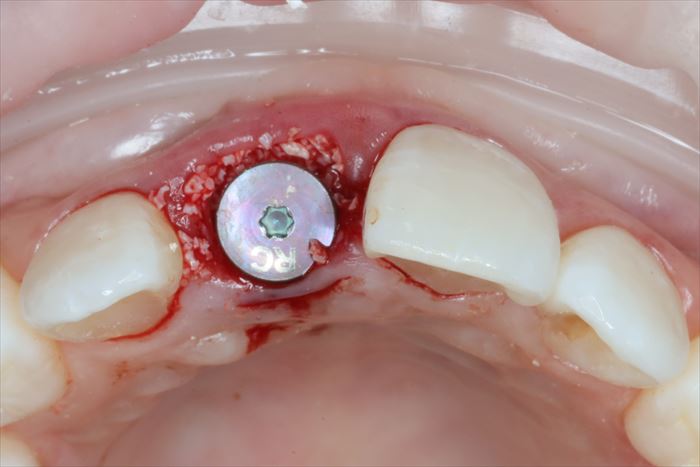

ヒーリングキャップを締結しました。

歯根の方がインプラントよりも太いため隙間が生じます。

わずかな隙間は血液が貯留して骨となることが判っていますが、念のため骨移植材を準備します。

_

骨吸収を防ぐ目的で私はハイドロキシアパタイトを混ぜた骨移植材を填入しています。

ハイドロキシアパタイトは生体内で吸収されにくく形態の保持に役立ちます。

表層にはコラーゲン使用人工骨であるボナーク®を掛け布団のように置いて、

骨移植材の顆粒が術後早期に流出することを防ぎます。

吸収性の縫合糸で縫合してインプラント埋入オペは終了です。